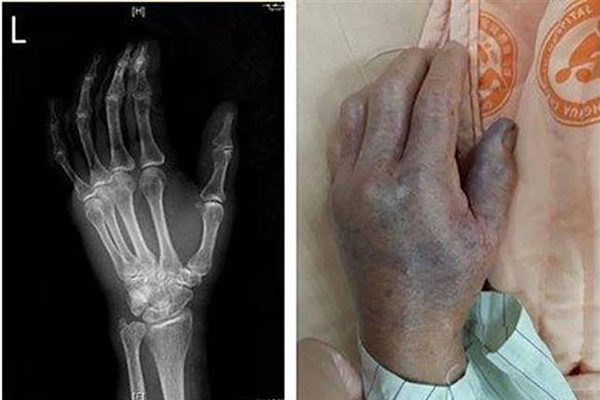

Theo báo chí Đài Loan đưa tin, một người phụ nữ ngoài 40 tuổi đã vô tình bị vảy cá đâm vào tay trái khi đang sơ chế cá sống. Vài giờ sau, vết thương nhỏ này phát triển thành viêm cân hoại tử. Sau khi đến bệnh viện kiểm tra, người này được chẩn đoán là nhiễm vi khuẩn Vibrio vulnificus, rất may là bệnh nhân đã bình phục và xuất viện sau khi cắt cụt chi và điều trị kháng sinh.

Lin Jixian, bác sĩ điều trị tại Khoa Y tế Cấp cứu và Chăm sóc đặc biệt của Bệnh viện Changji (Đài Loan) cho biết, một khi người bình thường bị nhiễm vi khuẩn Vibrio vulnificus, họ có thể gặp các triệu chứng như nôn mửa, tiêu chảy, đau bụng, rất dễ lây nhiễm và xâm nhập vào máu, có thể gây sốt, ớn lạnh, phồng rộp và hoại tử ở bàn tay và bàn chân, lan rộng vết thương, thậm chí sốc nhiễm trùng, với tỷ lệ tử vong lên đến 50%.